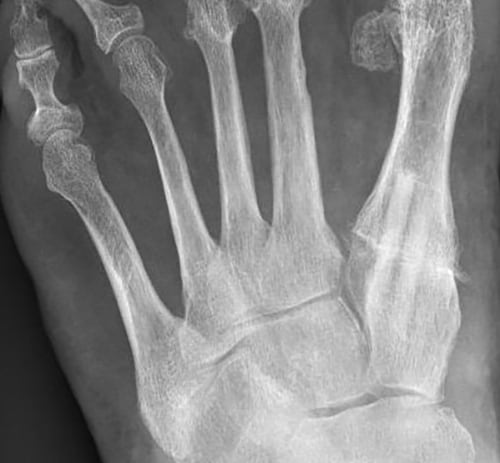

9 months postoperatively

Bone screw grafts only rudimentarily visible. Installation and remodeling without osteolyses

1 year postoperatively

Bone screw grafts have fused with the recipient bone. Radiologically no longer recognizable